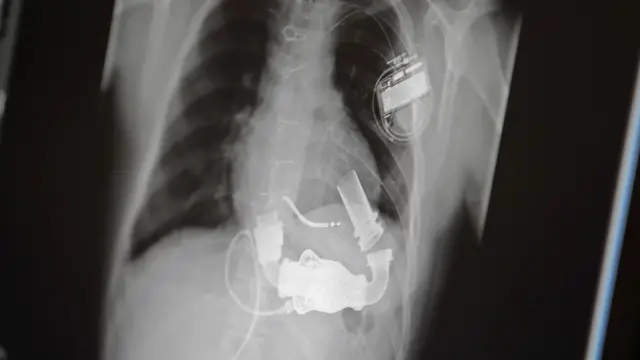

Safari ya ajabu ya miaka 61 ya wanasayansi kutengeneza moyo bandia

Mtu mzima wa miaka 47 alikuwa akifanyiwa upasuaji wa kurekebisha moyo wake uliokuwa umevimba kwenye kuta zake. Alikuwa akisaidiwa na mashine ya kupumua. Ungeondoa mashine angekufa kwa kuwa moyo ulikua dhaifu kabisa. Alihitaji sana kupandikizwa. Denton Cooley, mshirika wa DeBakey, alimwambia kuhusu kumuwekea moyo wa bandia wa majaribio na akakubali. Mgonjwa aliwekwa moyo huo kwa masaa 64 hadi moyo wa wafadhili unaolingana na wake ulipopatikana na kisha kupandikizwa.

Hii ilionekana mwanzoni kama ushindi mkubwa kwa ufanisi wa moyo bandia, lakini kwa kusikitisha mgonjwa alifariki masaa 32 baadaye kutokana na madhara. Kifaa hicho kilikuwa kimeharibu damu na figo zote mbili, na kuta za mifuko hiyo inayoweza kupanuka zilizungukwa na damu iliyoganda. Hii ilitangaza msururu wa matatizo ambayo yangeendelea kuzuia wanasayansi na wahandisi wanaopambana na utaratibu huu.

Moyo wa kwanza uliotengenezwa na Robert Jarvik, moja ya marudio ya wanasayansi yaliyofuata, uliwekwa kwa wagonjwa watano na mmoja aliishi kwa siku 620. Lakini wawili kati ya wagonjwa hao walipata viharusi vikali, na hatimaye wote walikufa kwa madhara au matatizo ya damu.

Mafanikio yamepatikana: utafiti mmoja uligundua asilimia 80% ya wagonjwa waliowekewa moyo wa bandia waliweza kuishi kwa zaidi ya mwaka mmoja, na wengine kwa miaka sita. Muda mrefu zaidi mgonjwa alisaidiwa kupandikizwa moyo ilikuwa siku 1,373. Lakini matatizo makubwa ya kuambukiza bado yalikuwa ya kawaida, na lengo la tiba kamili ya "marudio" kwa moyo wa bandia bado ilikuwa ndoto ya mbali.